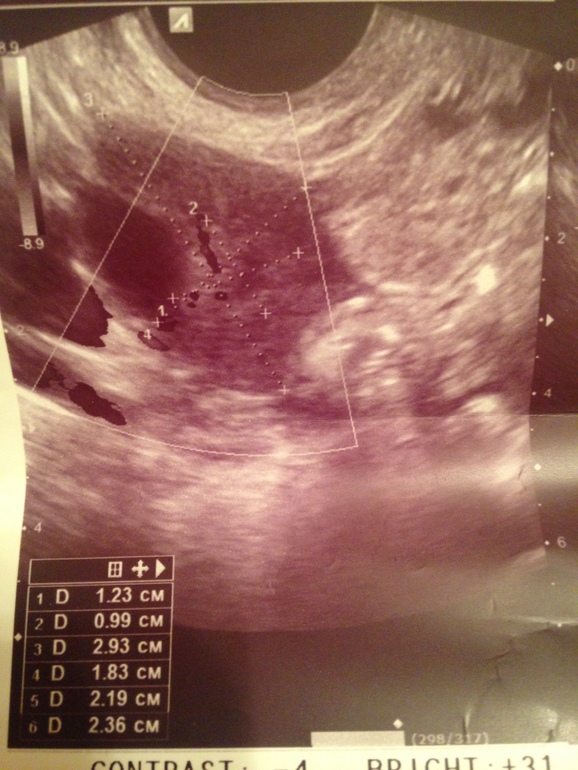

Я наверное уже надоела со своим УЗИ,но у меня вопрос:Можно ли спутать ЖТ с фолликулом который сдулся или с кистой??Просто врач сначала четко заявила ,что у меня ЖТ справа(1.2 см),потом нашла слева фоллик 2см и говорит,значит там не ЖТ,а что-то из того,что я выше написала ,но по форме как звезда и с кровотоком хорошим.

Перепутать вообще сложно, но можно. У Вас фото есть?

Вот это "нечто"